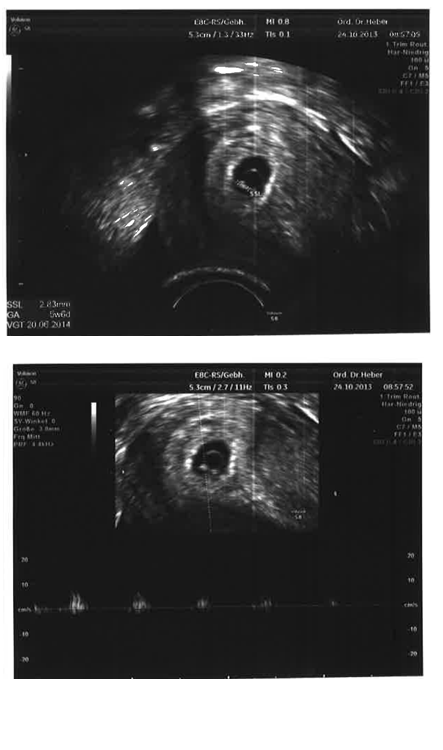

Guten Morgen Mädls.....darf ich presentieren klein Klümelchen :x

Wir sind laut Artzt heute 5+6....und es war der erste Tag an dem das Herzal geschlagen hat.... Er meinte jetzt setzen wir noch eines drauf und dann könnten wir es hören auch....es war soooo schönnn und PAPA war sooo stolz :x :x (das untere Bild is mit Herzrythmus) :x :x

Wir sind heute 2,83mm groß